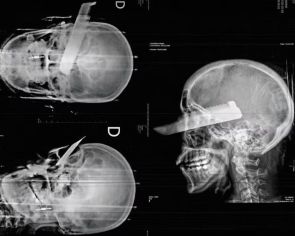

Mulher fica com faca presa no olho direito ao escapar de tentativa de feminicídio em SC

Depois das agressões, a vítima conseguiu fugir, pediu ajuda a vizinhos e foi socorrida. Companheiro de 26 anos foi preso em flagrante

Foto: Reprodução/Redes Sociais

De acordo com a Polícia Civil, a vítima foi atacada dentro de casa pelo companheiro, de 26 anos, e atingida por uma facada no rosto enquanto tentava fugir das agressões. Após o ataque, a mulher conseguiu escapar, pediu ajuda a vizinhos e acionou o socorro.

Ela foi atendida pelo Corpo de Bombeiros e encaminhada ao Hospital Regional do Oeste, em Chapecó. A vítima apresentava hematomas no rosto, no braço e na perna esquerda, além de uma lesão grave no olho direito. O estado de saúde não foi divulgado até o momento.